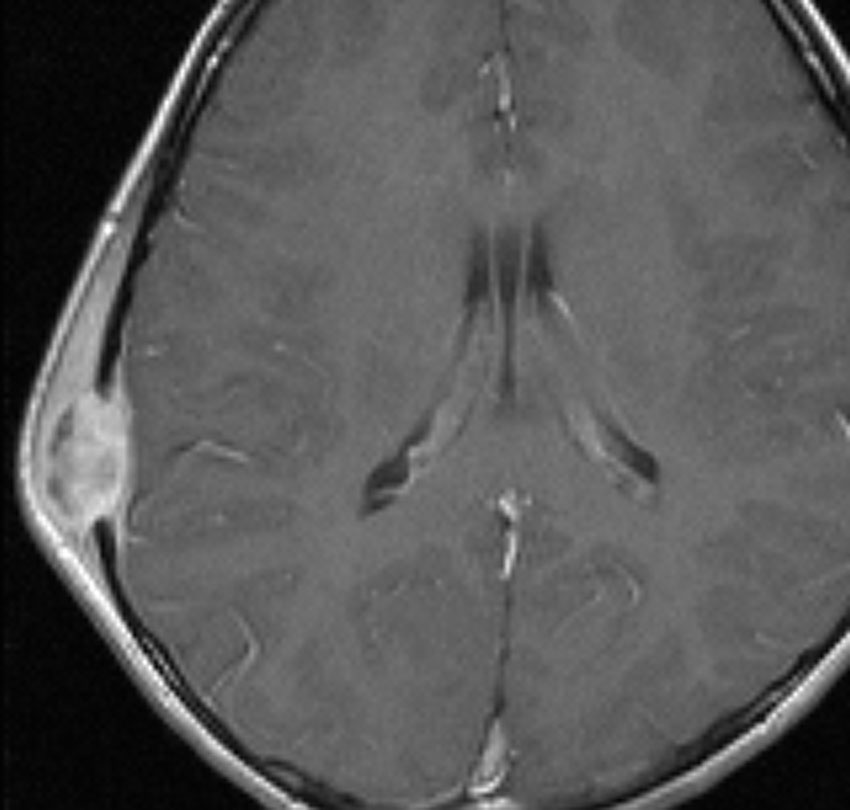

9歳の男の子です。右側頭部が腫れてきたのに気づきました。頭蓋骨のいびつな破壊像があります。

左はMRI T2強調画像です。まるで丸い腫瘍のように見えます。

下のT1強調画像では,ガドリニウム造影剤で強く増強されていて皮下に炎症性腫脹がみられ,活動期の病変であるのがわかります。

この病変は単発(孤発)病変ですが,ややいびつな形をしていて,頭皮の方に盛り上がっていますから,活動性の病変です。手術で完全摘出すると治りますから,骨欠損が広がるようなら手術したほうがいいです。理由は,手術が簡単なこと,病理診断がつくこと,これ以上の病変の広がりを抑えることです。最近は自然の骨に近いような人工骨で補填することができますが,骨形成しなくても自然修復で骨形成されます。とくに,低年齢児では骨形成をしない時もあります,頭蓋骨が自然再生するからです。